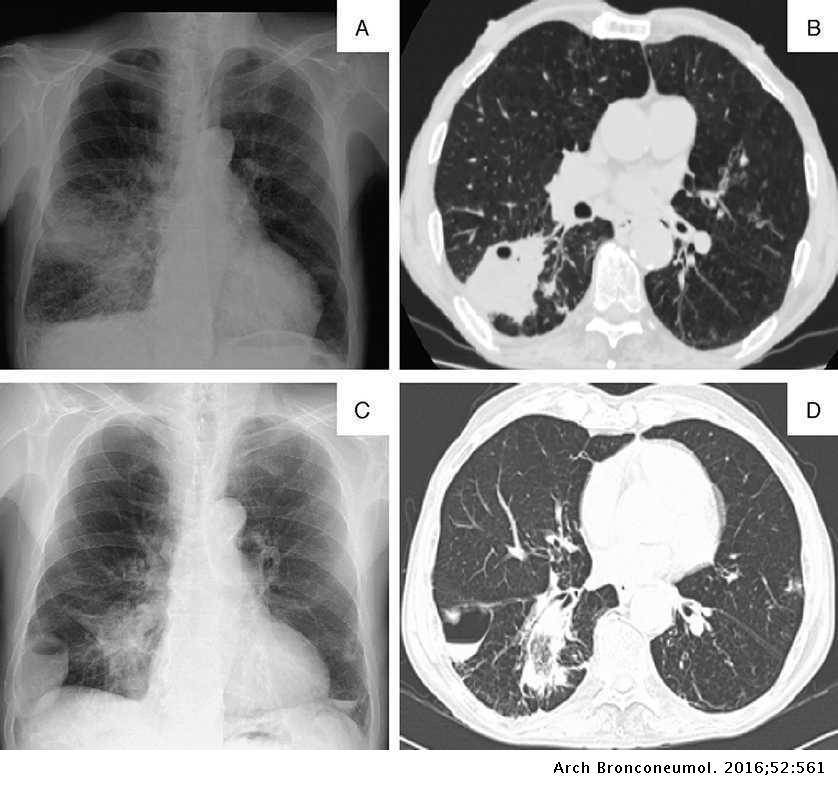

Es el aumento de la atenuación pulmonar, por ocupación del espacio aéreo alveolar por sangre, pus, agua o exudado:

Consolidación/alveolar

¿Cómo se ve la consolidación en Rx?

Radioopacidad irregular y mal definida

¿Cómo se ve la consolidación en TC?

Hipodensidad irregular y mal definida

Es la principal causa de consolidación:

Neumonía